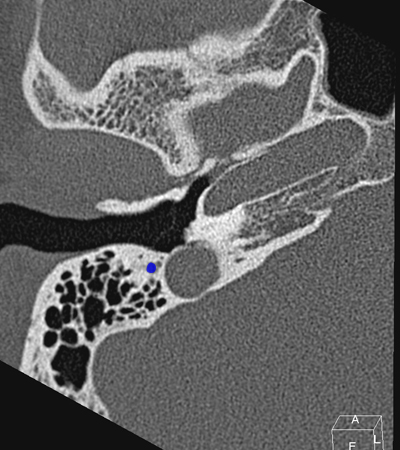

Horizontal petrous carotid Jugula bulb Sigmoid sinus Anterious wall of bony EAC (tympanic bone) Eustachian tube Tympanic membrane Facial nerve (f3), mastoid segment